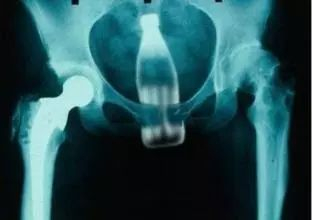

说到奇怪的患者,一定要说的是:

某些X光拍出来的东西也真是让人一言难尽

▼

不要问我这都是什么

我不知道